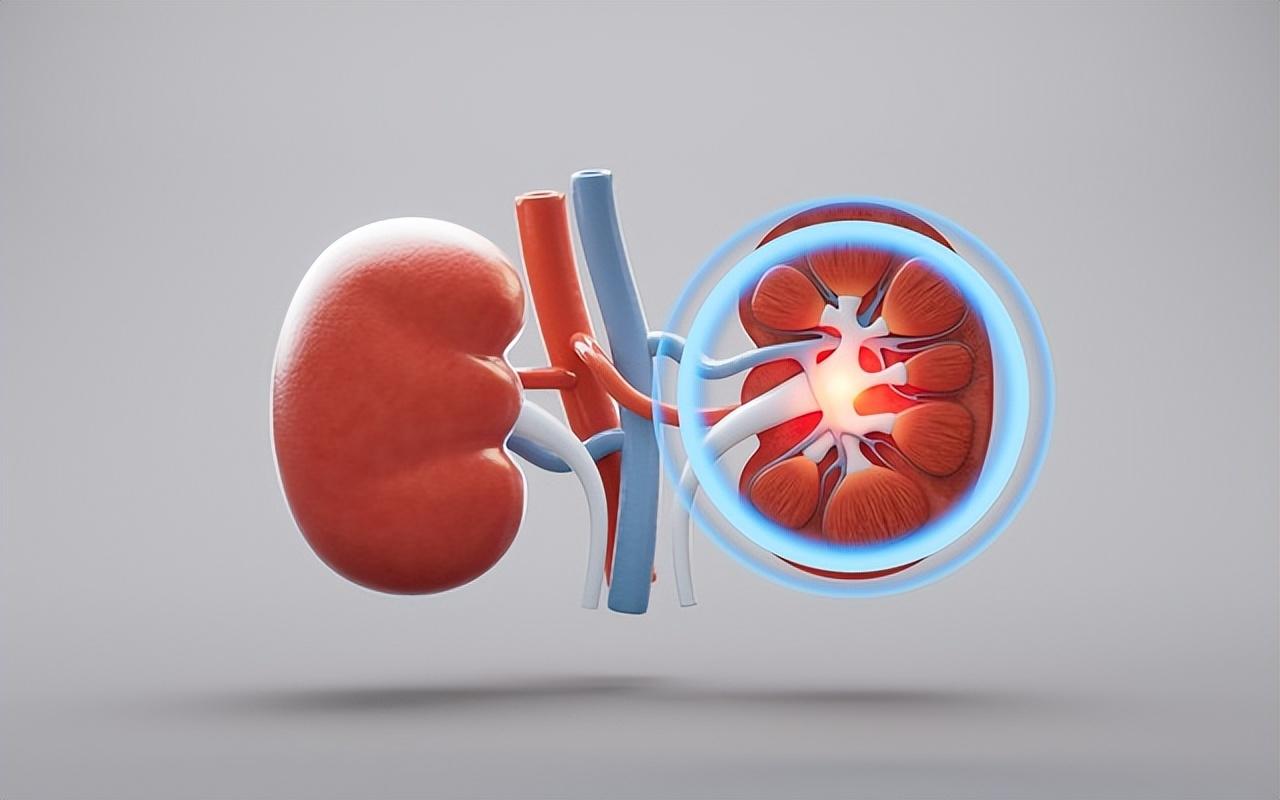

腎臟到底在幹什麼?

說人話。

腎臟就像24 小時運轉的淨水器:

- 把血液裏的毒素、廢物、多餘水分過濾掉

- 調節血壓

- 維持酸鹼平衡

- 還能幫你“造血”(促紅細胞生成素)

問題來了。

當腎臟一點點壞掉時,身體是很“能忍”的。

壞 30%,你可能沒感覺。

壞 50%,你還在上班。

等壞到 80% 以上,

纔開始“全面報警”。

而這一步,往往已經是尿毒症邊緣,甚至晚期。